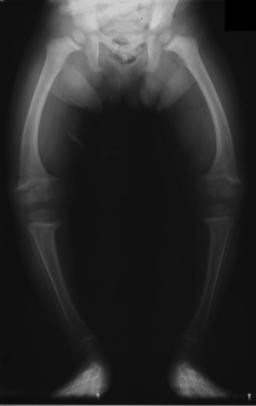

büyümekte olan iskeletin kalsifikasyon bozukluğu ile belirgin sağlıkla vitamin d eksikliği sonucu kalsiyum ve fosfor metabolizmasındaki bozukluk büyümenin yavaşlaması kemiklerin ve dişlerin niteliği ve şeklinin bozulması belirtileri ile seyreden hastalıktır.

raşitizm, çocuklarda genellikle aşırı ve uzun süreli d vitamini eksikliği nedeniyle görülen kemiklerin yumuşaması ve zayıflaması durumuna verilen isimdir.

genellikle d vitamini eksikliğine bağlı gelişen, 6/18 aylık çocuklarda görülen kemik hastalığı.

19. yüzyıl başlarında kuzey avrupa ülkelerinde doğan çocukların yaklaşık %90'ının 4 yaşına gelmeden ölmelerine yol açan raşitizm, omurga, kol ve bacak kemiklerinde biçim bozukluklarına yol açar.